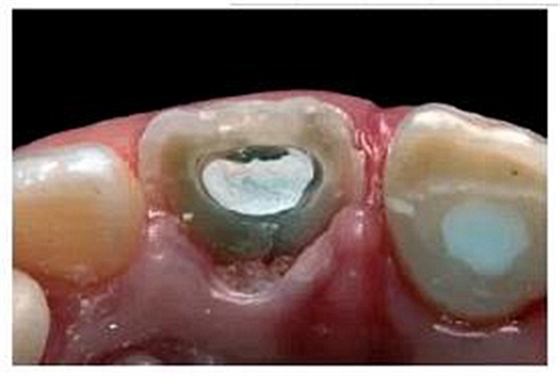

去除殘留的復(fù)合樹(shù)脂后,輕輕去除10mm長(zhǎng)的牙膠,操作時(shí)盡量避免損傷薄弱的根管壁。根據(jù)所需長(zhǎng)度,選擇6號(hào)成品FRCP放入根管內(nèi)。由于根管口較大,樁和根管壁間無(wú)法獲得足夠的固位力(圖12)。但填入樹(shù)脂粘接劑后,樁和根管壁之間的間隙則不會(huì)對(duì)FRCP的性能產(chǎn)生較大影響。粘接前需用乙醇清洗纖維樁表面。